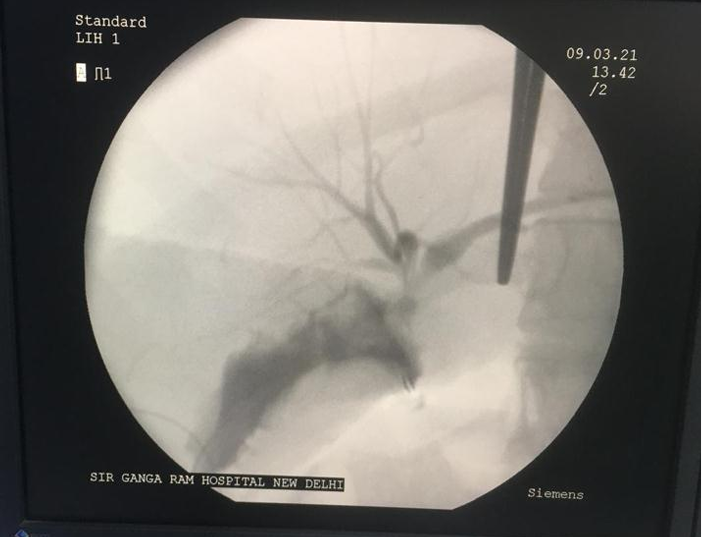

Figure 1. Illustration showing intraoperative cholangiogram delineating the anatomy.

Per-operative cholangiogram

Per operative cholangiogram was performed in 5 (8.3%) patients out of 60 in our study. This selective application is consistent with recommendations by Pesce et al. [24] and Giger et al. [25] who discussed the tailored use of intraoperative imaging techniques based on the specific type and severity of the bile duct injury. In their study, 8% of patients also underwent per operative cholangiogram. The infrequent use of per operative cholangiogram also reflects a broader trend in surgical practice, that it was performed when there was difficulty in delineating anatomy per operatively at the time of bile duct injury repair.